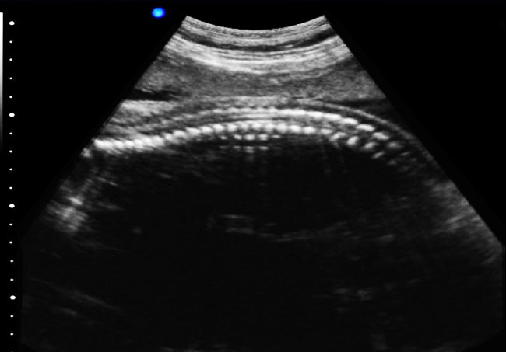

P5-VET獸用彩超機 P5-VET便攜筆記本獸用彩超機-寵物b超機掃描圖 P5-VET便攜筆記本獸用彩超機掃描圖